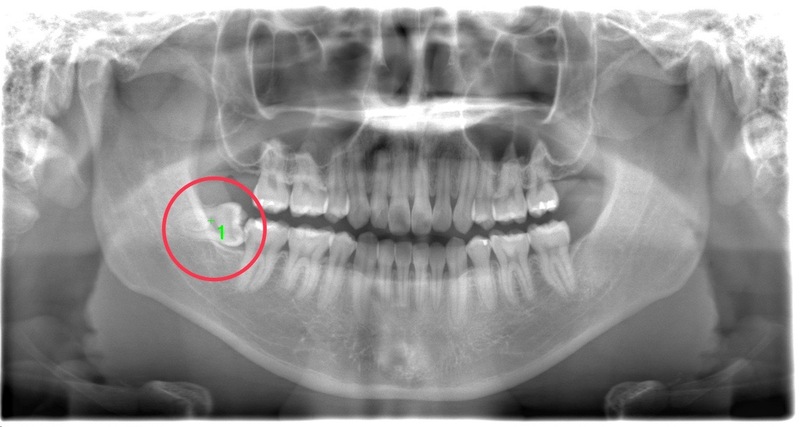

CASE 3

基本情報

| 年齢・性別 | 20代・男性 |

| 主訴 | 左下親知らず抜きたい |

| 親知らずのはえ方 | 半埋伏 |

| 抜歯期間 | 30分 |

| 抜歯費用 | 約2,500円(保険内) 別途CT撮影で3,000円 |

| 抜歯内容 | 左下の半埋伏親知らず抜歯 |